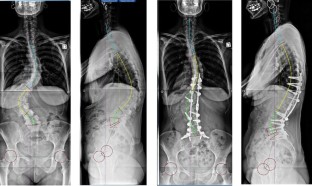

Clinical and radiological data were extracted from a prospective database of 132 AIS patients and 52 AS before and at last follow-up after surgical correction. Sagittal parameters were evaluated on AP and lateral radiographs using a custom software: pelvic incidence (PI), sacral slope (SS), pelvic tilt (PT), lumbar lordosis (LL), thoracic kyphosis (TK), C7 Barrey’s ratio, spino-sacral angle (SSA). A new algorithm of combination of balance parameters was proposed to characterize and compare the various pathological spino-pelvic settings. Based on PI subdivision in high (<55°) and low values (>55°), then on a range of PT indexed on PI giving the pelvis positioning (anteverted, normal or retroverted), the population was finally characterized by the C7 plumbline position with regard to the posterior edge of the sacrum and the center of the femoral heads, in balanced, slightly unbalanced and unbalanced. More specifically, the AIS study included the cervical shape alignment with cervical lordosis (CL) and sagittal thoracic profile assessment (hypo vs. normokyphotic). In AS, the study focused on thoraco-lumbar kyphosis (TLK) occurrence (LL length). Paired Student t tests were used for comparison (α = 0.02).

Results

Pre-operatively, in AIS there was a prevalence of lower PI (57 %). Whatever the PI, PT remained anteverted or normal. Positioning of C7 was much more unbalanced, forward of the femoral heads (50 %), than in asymptomatic population (17 %). There was a notable loss and reversal of cervical lordosis in the majority of subjects, with an average cervical kyphosis measurement of 10 ± 18°. Thoracic kyphosis values were lower than average, while lumbar lordosis values were within normal limits. After surgery, in the entire group, a slight but significant increase of PT coupled to a decrease of SS and LL was noted, while no changes could be documented in thoracic kyphosis and cervical lordosis. However, when sub-classified according to thoracic hypo versus normokyphosis pre-op, there was a significant decrease of TK coupled to a decrease of LL and CL in the normokyphotic group, while TK and CL were improved in the hypokyphotic group. A significant number of patients improved their global balance. Changes in sagittal profile between Lenke curve types were minimal. In AS there were significant differences between low and high PI populations. Severity of unbalance increased in high PI population with association of retroverted pelvis and forward unbalance. In lower PI, increasing PT was generally sufficient to balance the patients. The occurrence of TLK was strongly increased in the entire population and became the rule in those with lower PI (76 %). Post-operatively, in those with high PI, PT did not change while global balance improved slightly. The strategy of correction in higher PI was to maintain TLK. In those with low PI, PT improved while C7 did not change. Correction of TLK was obtained in eight cases.